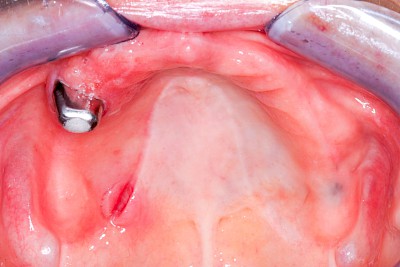

Druckstelle / Lappenfibrom

Eine besondere Form der Verletzung entsteht, wenn eine Zahnprothese ungleichmäßig und punktuell auf Kieferbereiche drückt. Die sogenannten Druckstellen erscheinen wie kleine Druckgeschwüre (vergleichbar dem Dekubitus z. B. an Fersen oder im Bereich der Hüftknochen) auf.

In selteten Fällen kann es auch zu faltenartigen Aufwerfungen der Schleimhäute im Bereich der Prothesenränder kommen. Diese besondere Erscheinungsform der Prothesen-Druckstelle wird auch als Lappenfibrom bezeichnet. Die Schleimhäute fallen dabei in der Regel nicht durch starke Rötungen oder ein Ulcus auffallen.